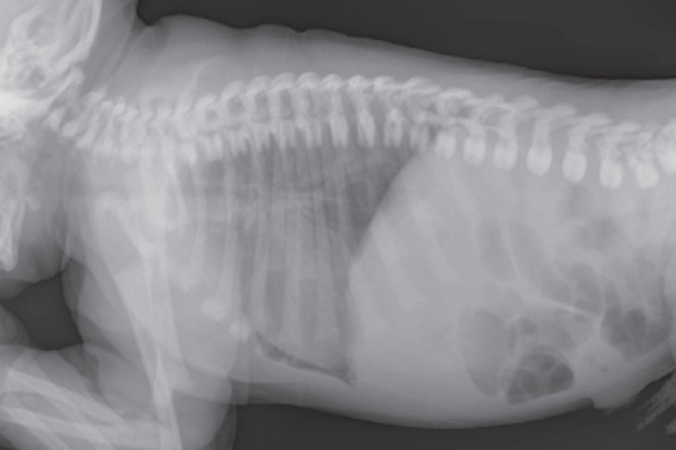

Lateral chest radiograph showed a prominent lucency in the anterior cardiophrenic angle (Figure 1). On anteroposterior radiograph, a small, thin rim of lucency was visible along the right heart border.

The radiographic lucent regions were thought to likely represent a small pneumopericardium. The infant was monitored closely in the nursery and remained asymptomatic. Follow-up echocardiography on day 3 showed normal parasternal and apical views, suggesting resolution of the pneumopericardium.